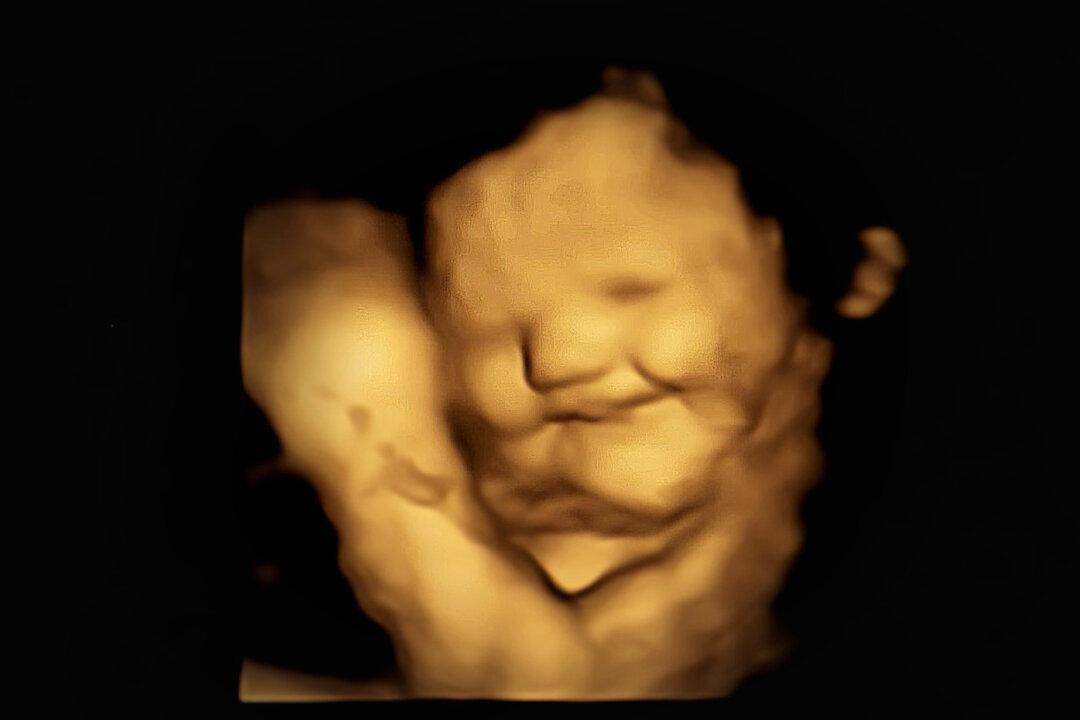

To some parents, it surely comes as no surprise: Babies in the womb can express delight and displeasure on their faces in correlation to the flavors their moms consume, a UK study found.

Using coded 4-D ultrasound scans, researchers identified complex facial movements in babies who were subjected to carrot (a sweet vegetable) and kale (a bitter vegetable) and confirmed their hypothesis to be correct: fetuses subjected to carrots showed more smiles; those subjected to kale showed more cry faces. Fetal facial movements were measured frame by frame, revealing reactions to maternal ingestion.